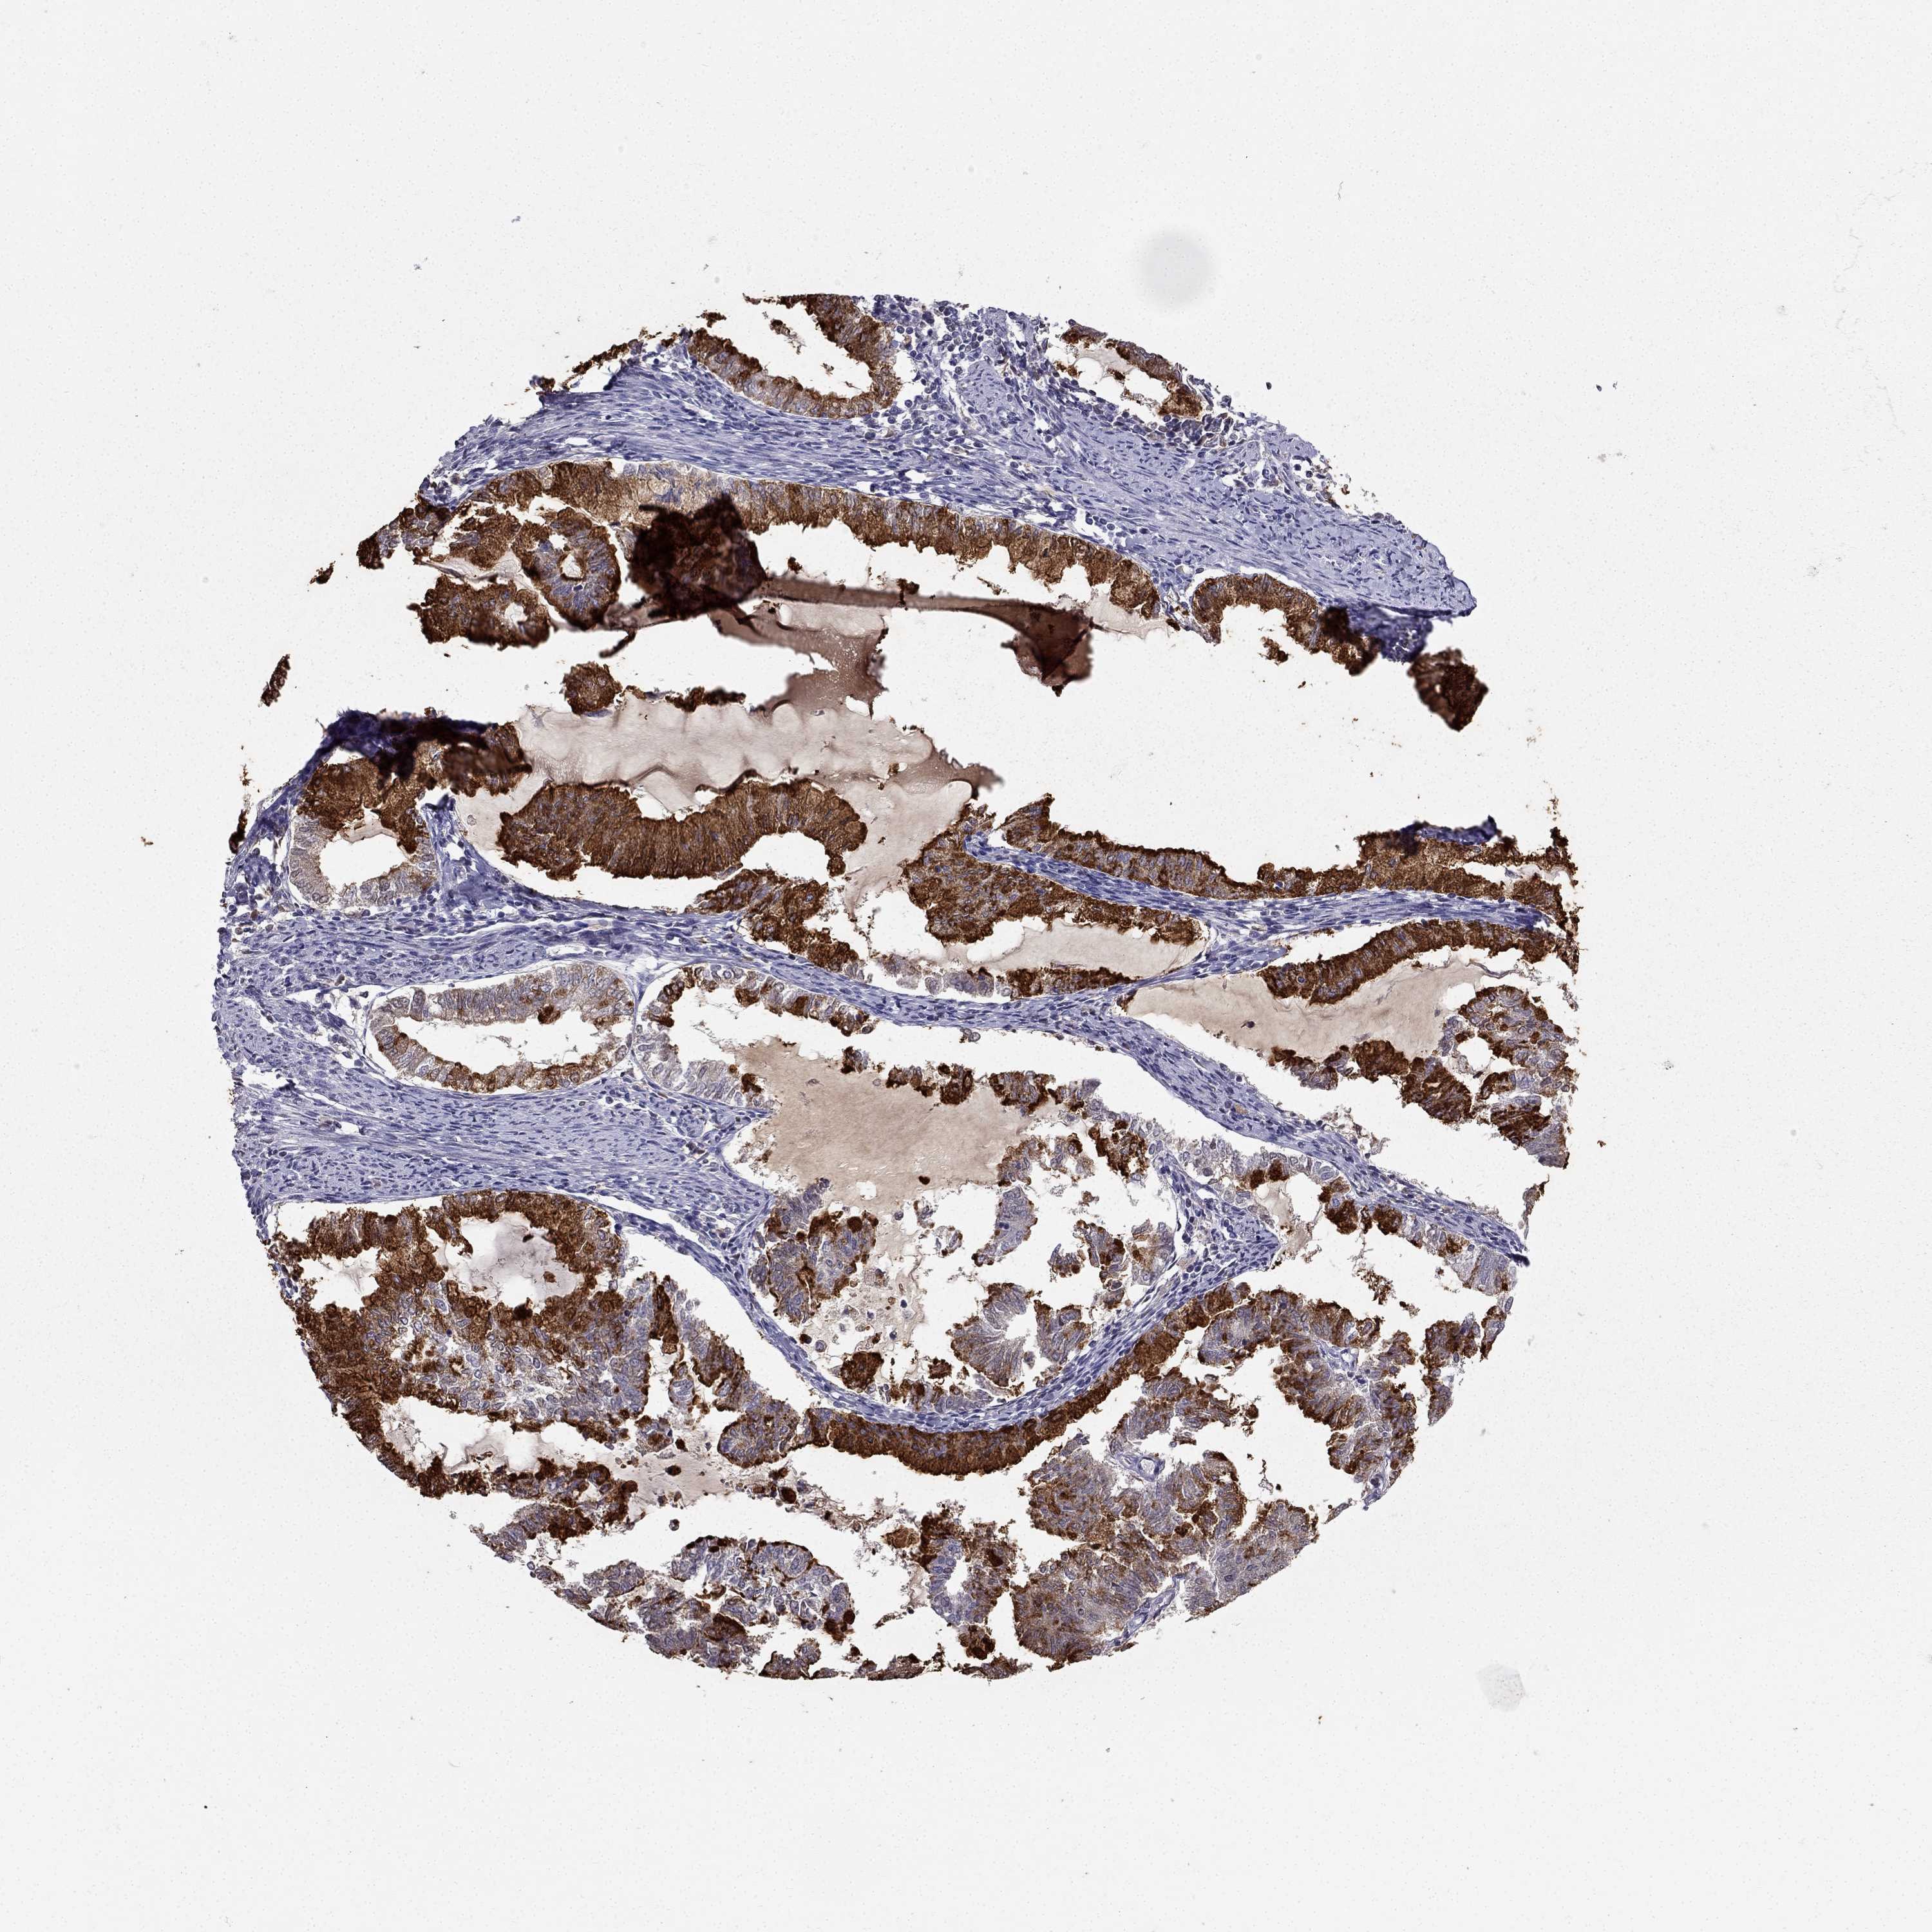

ENDOMETRIAL CANCER - Protein expressioni

A mouse-over function shows sample information and annotation data. Click on an image to view it in a full screen mode. Samples can be filtered based on level of antibody staining by selecting one or several of the following categories: high, medium, low and not detected. The assay and annotation is described here.

Note that samples used for immunohistochemistry by the Human Protein Atlas do not correspond to samples in the TCGA dataset.

Antibody stainingi

Antibody staining in the annotated cell types in the current human tissue is reported as not detected, low, medium, or high, based on conventional immunohistochemistry profiling in selected tissues. This score is based on the combination of the staining intensity and fraction of stained cells.

Each image is clickable and will lead to virtual microscopy that enables deeper exploration of all samples and also displays staining intensity scores, fraction scores and subcellular localization as well as patient and tissue information for each sample.

Antibody HPA035464

Antibody CAB020681

Staining

High

Medium

Low

Not detected

Intensity

Strong

Moderate

Weak

Negative

Quantity

>75%

75%-25%

<25%

None

Location

Nuclear

Cytoplasmic/membranous

Cytoplasmic/membranous,nuclear

Neoplasm, malignant, NOS